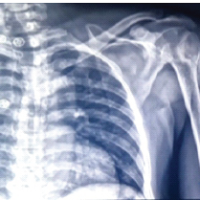

Histopathology confirmed the diagnosis of a benign osteochondroma with no evidence of malignant transformation. At 6-week follow-up, the surgical wound had healed satisfactorily, with restoration of scapular contour and significant improvement in shoulder range of motion. Post-operative radiographs confirmed complete excision of the lesion (Fig. 5), and clinical evaluation at 6 weeks showed restoration of scapular contour (Fig. 6), the patient returned to routine activities without restriction.

Figure 5: Immediate post-operative shoulder radiograph. Immediate post-operative radiograph of the left shoulder in anteroposterior view, obtained following surgical excision, confirming complete removal of the scapular lesion with restoration of normal scapular contour.